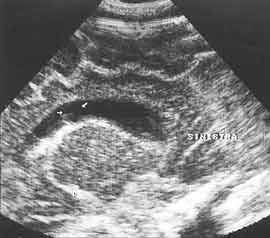

Рис. 4. Клебсиелезный менингит. Гнойный выпот на сосудистом сплетении в переднем роге (стрелки).